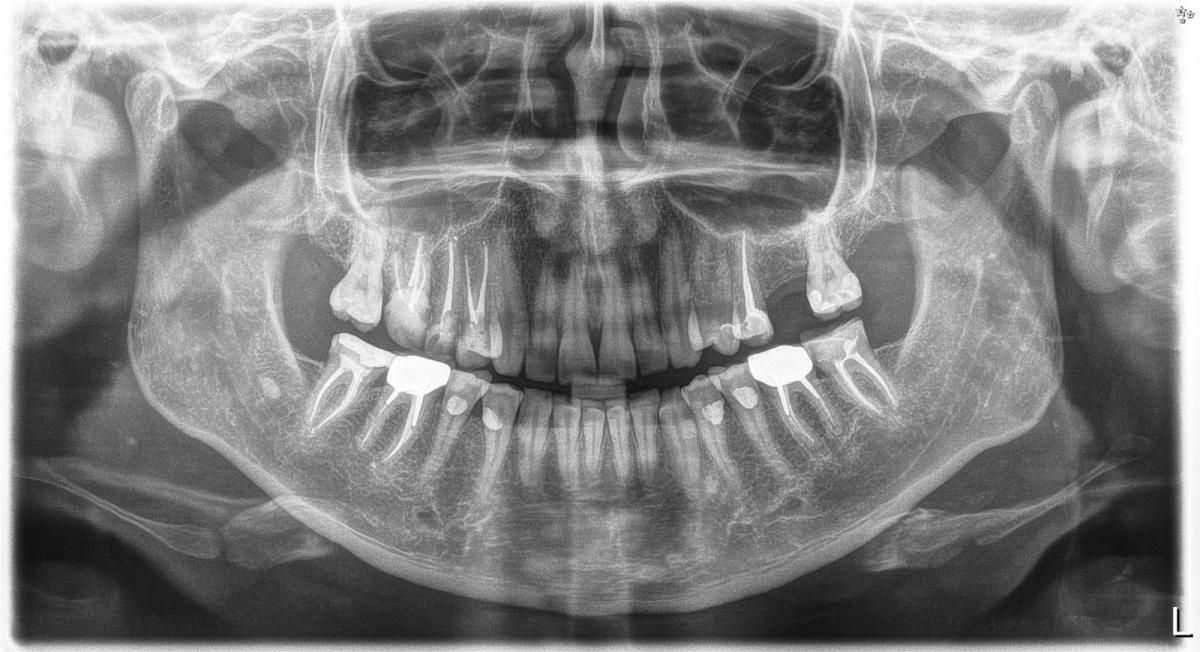

Здравствуйте, живу не в РФ сейчас. Проблема такова: за три месяца четвертый раз гайморит. Лор послал к стоматологу. Мой стоматолог ( по кт ) сказал проблем нет. Но доверия ответ не вызывает , так как была уже проблема тоже долгий гайморит, в итоге киста на корне щуба оказалась. Сразу скажу, сходила бы к другому стоматологу дополнительно, но принять в ближайшее время не могу.

Вопрос мой вот в чем: есть ли проблема с зубами по снимку?

Представленный Вами снимок, не даёт возможности ответить на поставленные вопросы.

добрый день! Тот снимок что вы прислали ОПТГ называется

Мария Борисова, добрый день, Мария. Вот еще картинка. Если вам не сложно, посмотрите, пожалуйста. У меня гацморит и фронтит левосторонний постоянно